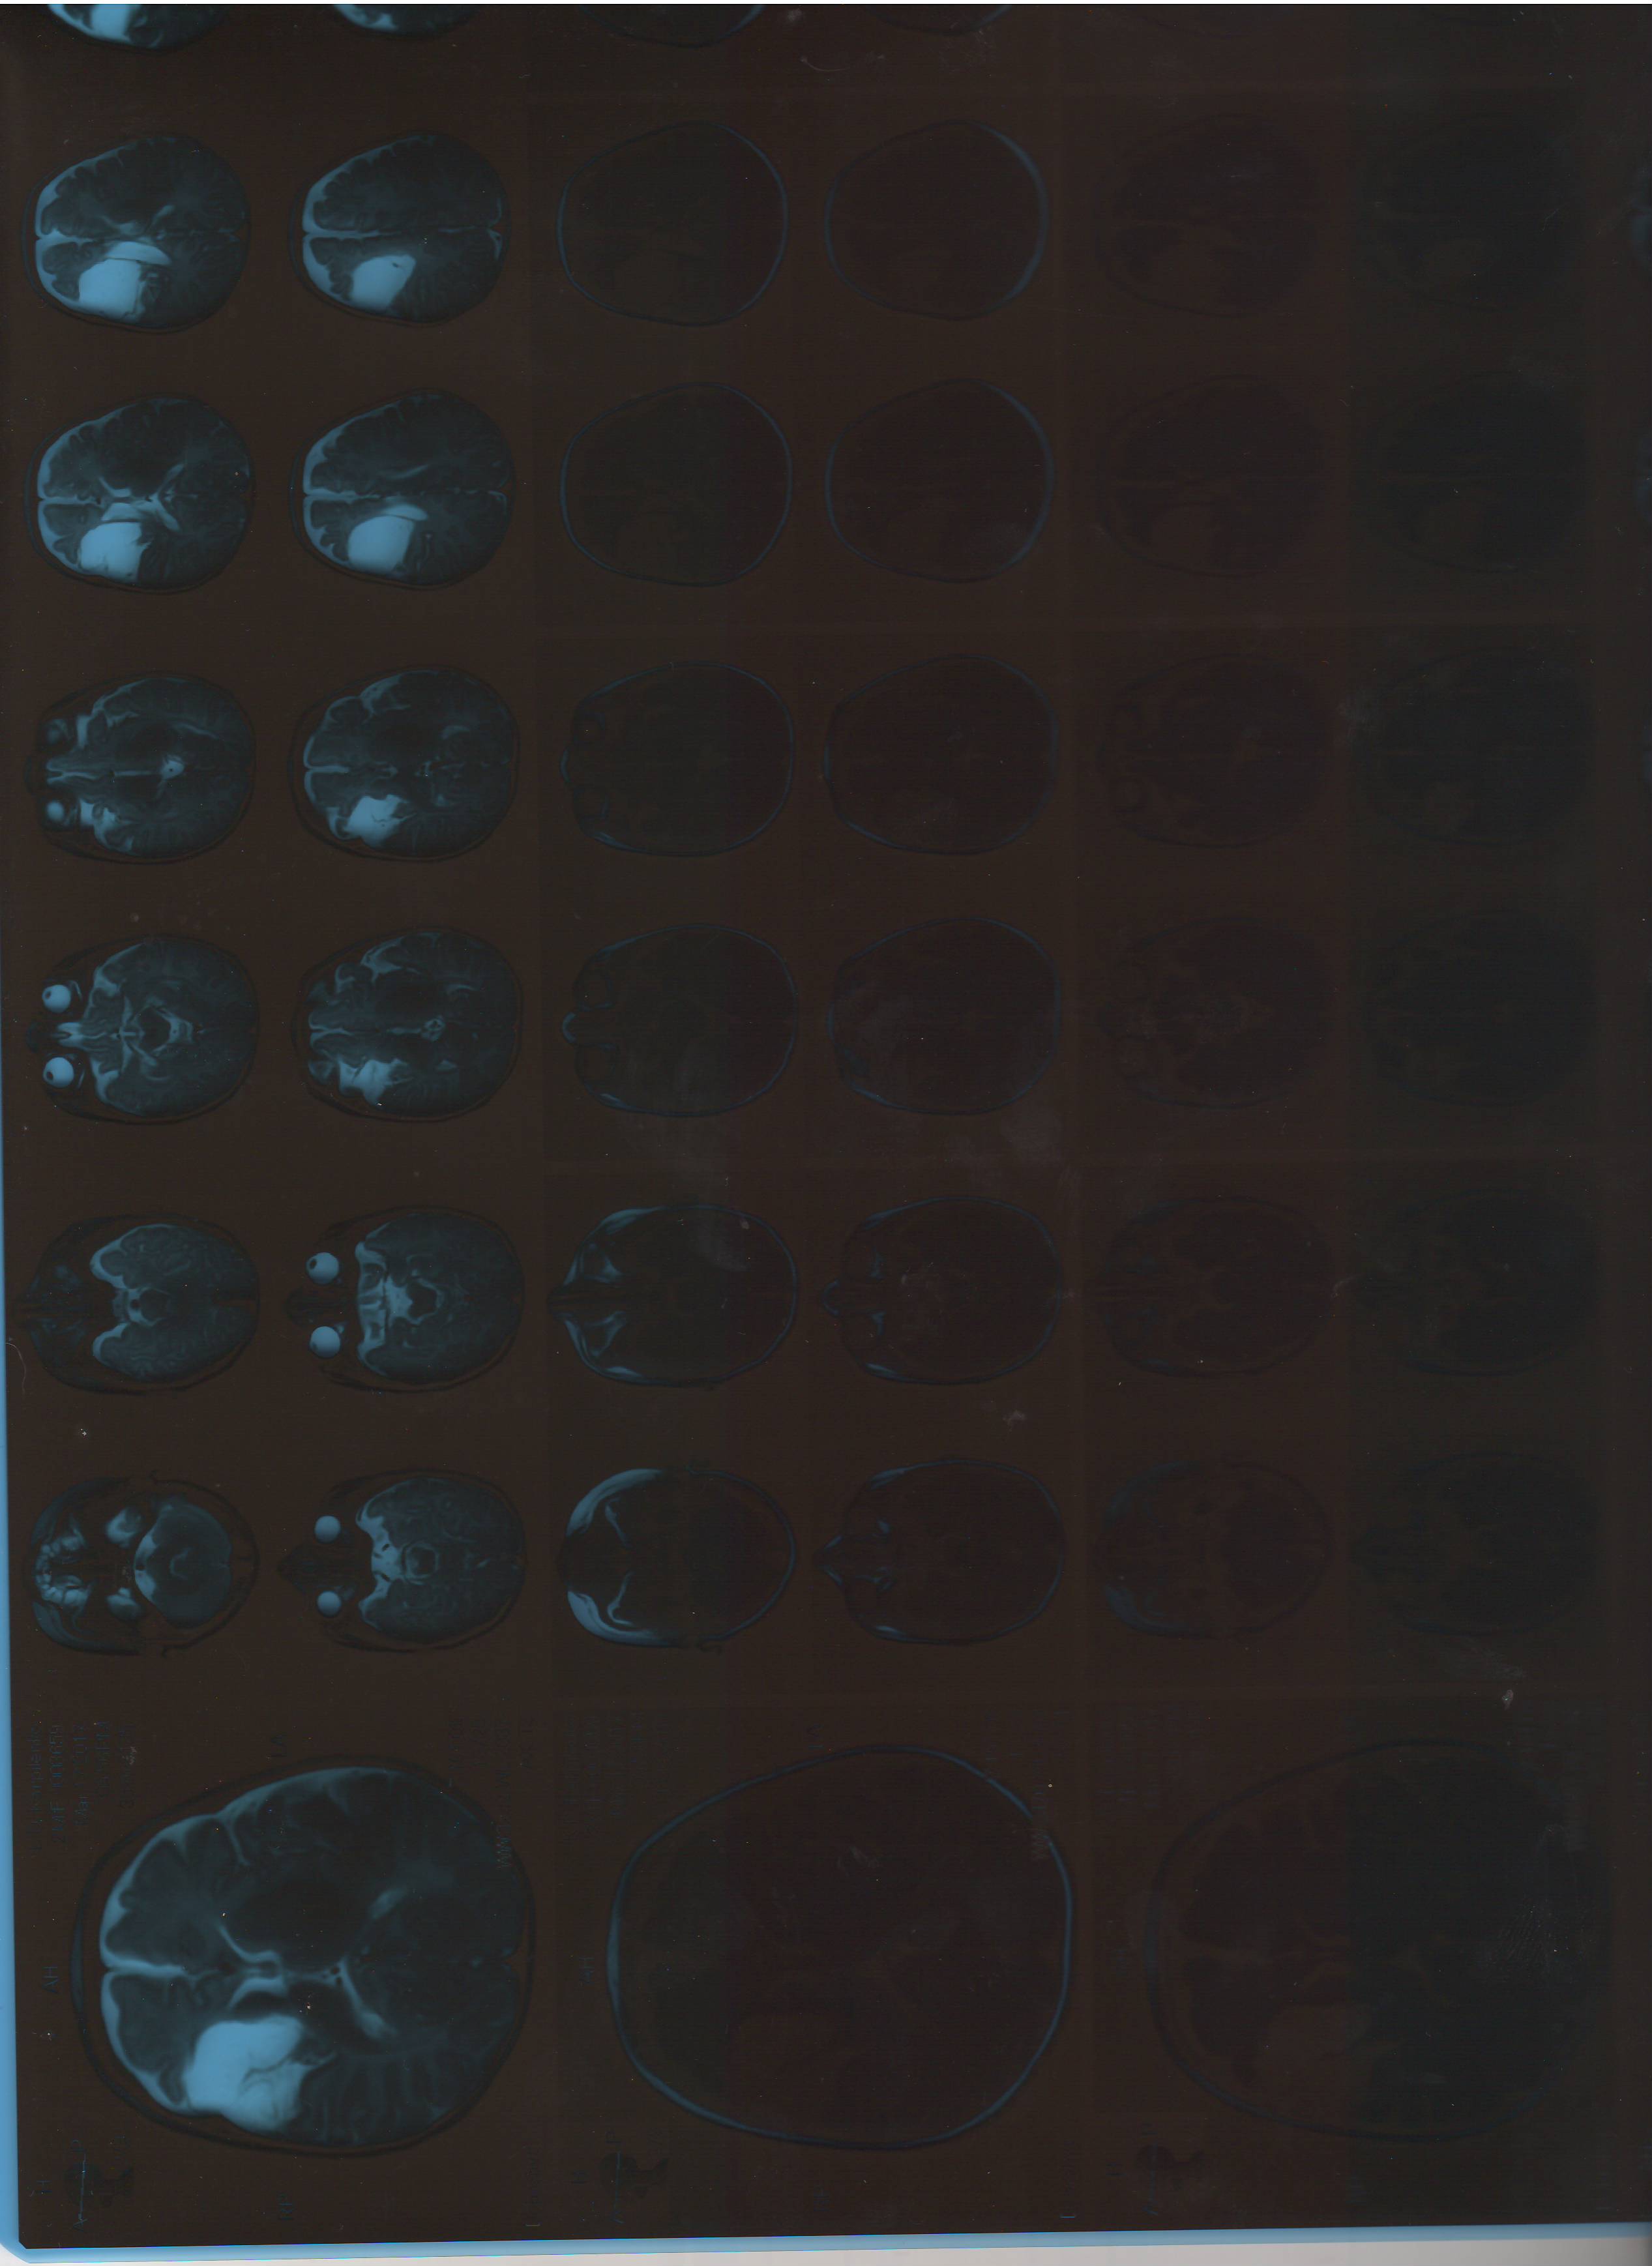

Суть проблемы - у ребенка большая порэнцефалическая киста в правой лобно-височной части 3,9*4,4*3,3 см, ребенку 2,5 месяца . Детали - ниже.

Через 4 дня Было сделано МРТ головного мозга (в 2,5 месяцев) и киста стала больше ,либо аппарат УЗИ показал не верные размеры.

ЗАКЛЮЧЕНИЕ: порэнцефалическая киста правой лобной части размер 3,9*4,4*3,3 [/color]сантиметра. Средние структуры головного мозга на уровне межполушарной перепонки смещены вправо на 2,5мм

Конвекситальные пространства прослеживаются на всем протяжении, равномерные, незначительно расширены в лобно-теменных отделах до 7мм

Связь с желудочной системой не выявлена. Тело и передний рог правого бокового желудочка траекционно подтянуты к кисте. Желудочки не расширены, тело боковых несимметричные. Ликвородинамика не нарушена. Дифференциация серого и белого вещества сохранена. Признаков внутричерепных гематом нет.

Мозолистое тело обычной толщины. Солярные, паросолярные структуры не изменены. Гипофиз не увеличен. Краниовертебральный переход не изменен. Миндалины мозжечка расположены над большим затылочным отверстием. Пирамиды височных костей обычной визуализации

11. MRT 17.03.2017.JPG

13. MRT 17.03.2017 (3).JPG

12. MRT 17.03.2017 (2).JPG